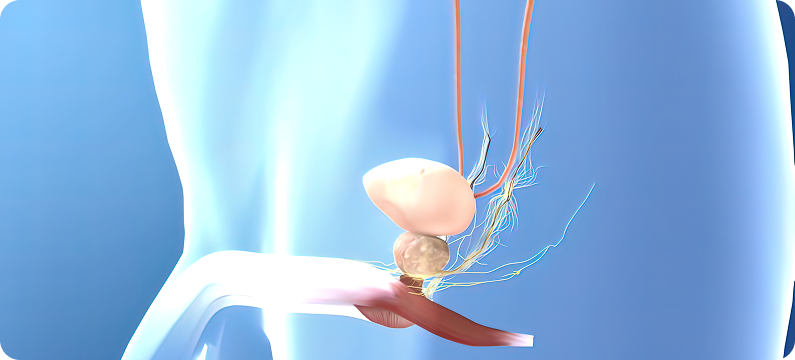

유방 · 전립선초음파는 여성의 유방 질환과 남성의 전립선 질환을 초음파로 정밀하게 확인하여,

방사선 노출 없이 안전하게 시행할 수 있어 조기 진단과 추적 관찰에 매우 중요한 검사입니다.

유방과 전립선은 다양한 질환이 발생하기 쉬운 부위로, 조기 발견 여부에 따라 치료 경과가 크게 달라집니다.

정기적인 유방 · 전립선초음파 검사는 이상을 조기에 확인하고 적절한 치료로 이어지는 가장 효과적인 방법입니다.

소변을 보기가 힘들거나 너무 자주 보시는 분

소변을 볼 때 통증이 있거나 잔뇨감이 있으신 분

정액에 혈액이 섞여 나오시는 분

아랫배, 골반 부위, 허리의 만성적인 통증이 있으신 분

음경이나 요도의 불편함, 작열감, 통증이 있으신 분

발기유지 기능 감소, 성욕 감소, 조루증이 느껴지시는 분